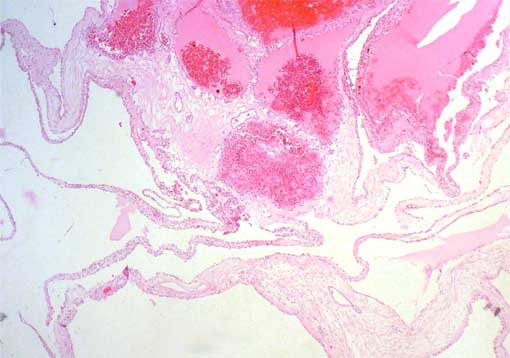

Figura 2.

H&E, X100.

No se encontraron áreas sólidas

con células claras ni había parénquima renal en los

septos.